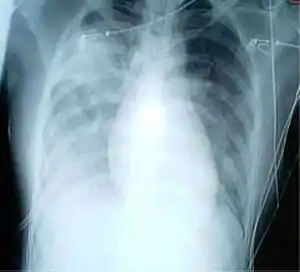

Síndrome respiratória aguda grave (SARS, do inglês Severe Acute Respiratory Syndrome, ou SRAG, em português) é uma doença respiratória viral de origem zoonótica causada pelo coronavírus SARS-CoV.[1][2] A doença causa sintomas semelhantes aos da gripe, como febre, dores de cabeça, calafrios e dores musculares.[1] No entanto, a SARS é uma doença muito mais grave do que a maioria das outras infeções por coronavírus, que geralmente causam apenas sintomas ligeiros.[1]

A SARS é causada pela infeção com o coronavírus SARS-CoV.[1] A transmissão entre pessoas dá-se por contacto próximo com a pessoa infetada ou através de gotículas expelidas pela tosse ou espirros de uma pessoa infetada.[1] Suspeita-se de diagnóstico de SARS nos casos em que a pessoa tenha sido exposta a uma pessoa infetada e tiver febre acompanhada de tosse ou dificuldades respiratórias.[1] O diagnóstico pode ser confirmado com exames para identificar o vírus.[1]

O tratamento consiste em isolamento, administração de oxigénio e, em caso de dificuldades respiratórias, ventilação mecânica.[1] A maioria das pessoas recupera ao fim de uma a duas semanas.[1] No entanto, a doença é fatal em cerca de 10 por cento dos casos.[1]